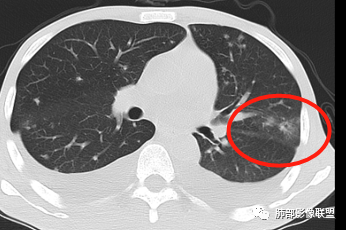

2.双肺散在不规则小片状影及结节影,部分可见磨玻璃晕。结节影边界较清楚。左肺片影边界不清,范围较大,支气管相关,支气管壁增厚不明显,病灶内见液化空洞。

3.肺炎型肺部影像学表现常为双肺多发片影,肉芽肿样结节影,边界相对清楚,可见磨玻璃晕,部分病灶可显示坏死空洞。部分病例出现胸水。支气管炎型病例可见较广泛支气管壁增厚。

有统计表明,干细胞移植患者双肺常以肉芽肿结节为主要表现。

4.应当注意肺外组织器官病灶的发现,如肝脏多发小脓肿及脾脏多发低密度结节影等,出现于白念珠菌的这些肺外小脓肿颇具特色,可以类似转移瘤的“牛眼征”,宜结合临床及病史综合判断。